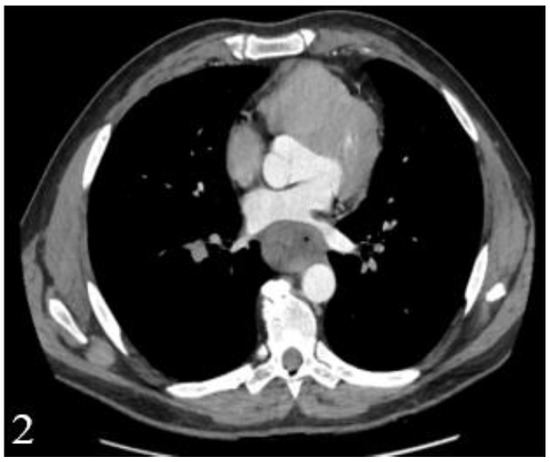

Figure 2.

Postcontrast CT, arterial phase, axial plane. Stenosing tumor of the distal esophagus and gastroesophageal junction that is tangent to the intrathoracic descending aorta and partially compresses the left pulmonary vein with no obvious signs of macroscopic invasion.